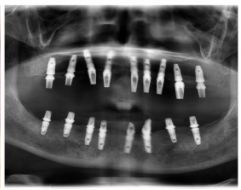

種牙后X光片,未戴冠。

通過X光片可以看到,醫(yī)生雖然盡量設計連冠種植,但還是用了十七個植體,盡管已經(jīng)是多次調整后的精簡方案,但手術時長依然長達一天。位老先生之前在另一家醫(yī)院咨詢時,醫(yī)生給的方案是種二十二個植體,光是種植費用就令人大呼“害怕”了。

種植修復后X光片

這一位老先生則選擇了All-on-4種植技術,即拔即種,上下頜分別種植4個植體就完成了全口牙齒修復,費用降低了不少,而且創(chuàng)傷小,恢復快。